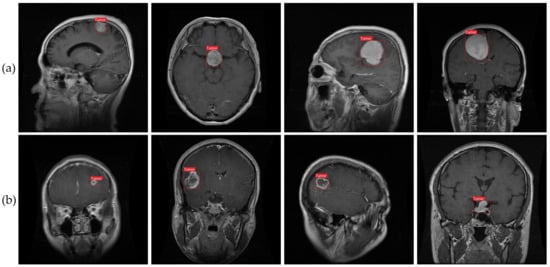

As seen in Figure 1 and described in [9], meningioma, glioma, and pituitary tumors are the most frequent primary brain tumors seen in clinical practice. Most cases of meningioma arise near the meninges tissues on the periphery of the brain or spinal cord [10]. This benign tumor develops in the membranes that rescue the brain and spinal cord. However, glioma, the brain tumor with the highest fatality rate [11], develops from the glial cells that surround and support the neurons. About a third of all cases of brain tumors are gliomas. Benign pituitary tumors develop inside the pituitary gland [12]. Prognosis and treatment options for brain tumors depend on a correct diagnosis. However, conventional biopsy techniques are painful, time-consuming, and fraught with inaccuracy in sampling [13,14]. Histopathological tumor grading (Biopsy) has its own set of problems, including intra-tumor heterogeneity and differences in the subjective assessments of different experts [15]. The diagnostic process for tumors is made more difficult and restrictive by these characteristics.

To ensure the validity of our findings, we used an openly available MRI dataset obtained from kaggle.com [64,65]. MRI scan images are included in this collection, since they are the gold standard for diagnosing brain tumors. Glioma (2548 images), pituitary (2658 images), meningioma (2582 images), and no tumor (2500 images) were the four subsets that made up our dataset of brain tumors. Images were all scaled to 512 pixels on the horizontal and vertical dimensions. We used 8232 MRI images (or 80% of the dataset) for training in our analysis, whereas 2056 MRI images (or 20% of the dataset) were set aside for testing. Brain tumor photos from various categories are shown as examples in Figure 1. For each type of brain cancer (glioma, pituitary, and meningioma), Table 1 provides the number of pictures in various views such as axial, coronal and sagittal. It is important to keep in mind that medical photos, in contrast to natural images, are more complicated and necessitate a greater level of skill to ensure appropriate analysis and interpretation. The brain tumor dataset was labeled with oversight from a medical specialist to ensure precision and consistency. This physician’s expertise was crucial, as it established criteria for how the dataset should be labeled. However, not all brain cancers have characteristic imaging findings; therefore, depending entirely on image analysis can be risky. As a result, pathology analysis is essential for diagnosing brain cancers. Our dataset featured abnormal language descriptions annotated by a medical expert to give rich context for model training. A larger amount of training data aids in the creation of more reliable models. Data augmentation strategies can be used to increase the diversity of the training samples when the volume of available data is low. To improve a model’s generalizability, data augmentation can be used to generate new variants of the existing data. In conclusion, our model’s predictive power was enhanced by the incorporation of extensive labeled data, curated by medical experts. To further improve the prediction models’ accuracy and reliability, data augmentation techniques can be used to increase the diversity of the training samples.

This study introduced an enhanced YOLOv7 model for accurately detecting multiclass brain tumors, specifically meningioma, glioma, and pituitary tumors, as visually depicted in Figure 1 and Figure 11. Our proposed model was carefully optimized, incorporating the CBAM attention mechanism and the SPPF+ and BiFPN components. The model was trained by employing MRI images acquired through T1-weighted contrast-enhanced sequences, harnessing the enhanced anatomical insights facilitated by contrast agents.